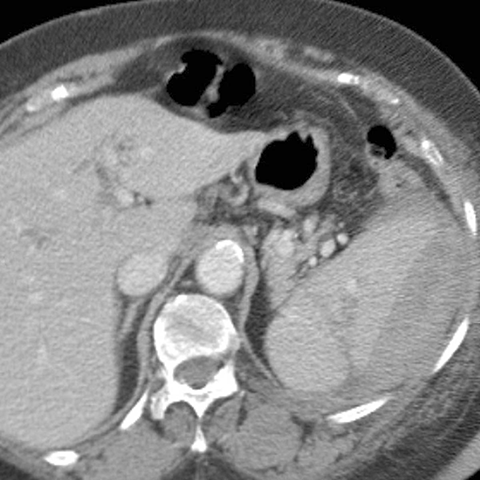

23-year-old male presents with blunt abdominal trauma after a motor vehicle accident [2 of 3]